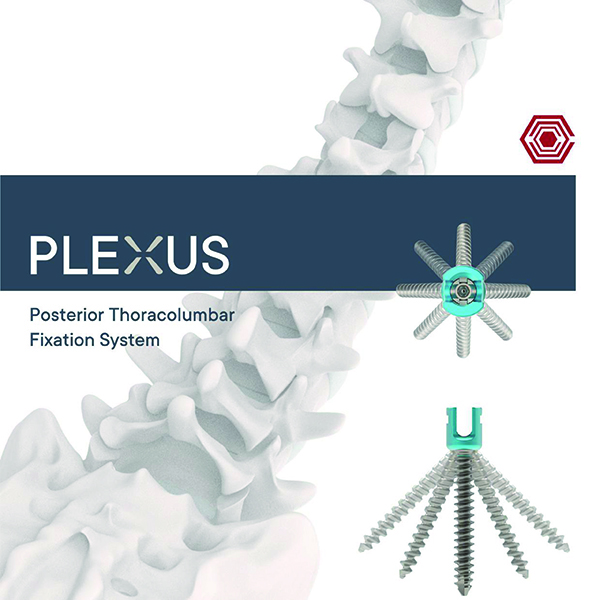

Plexus

Akif Kaya Aybek

Norm Akademi

- Surgical Techniques

- Implant Types

- Instrument Container

- Instrument Types

- Plexus Cerrahi Teknik